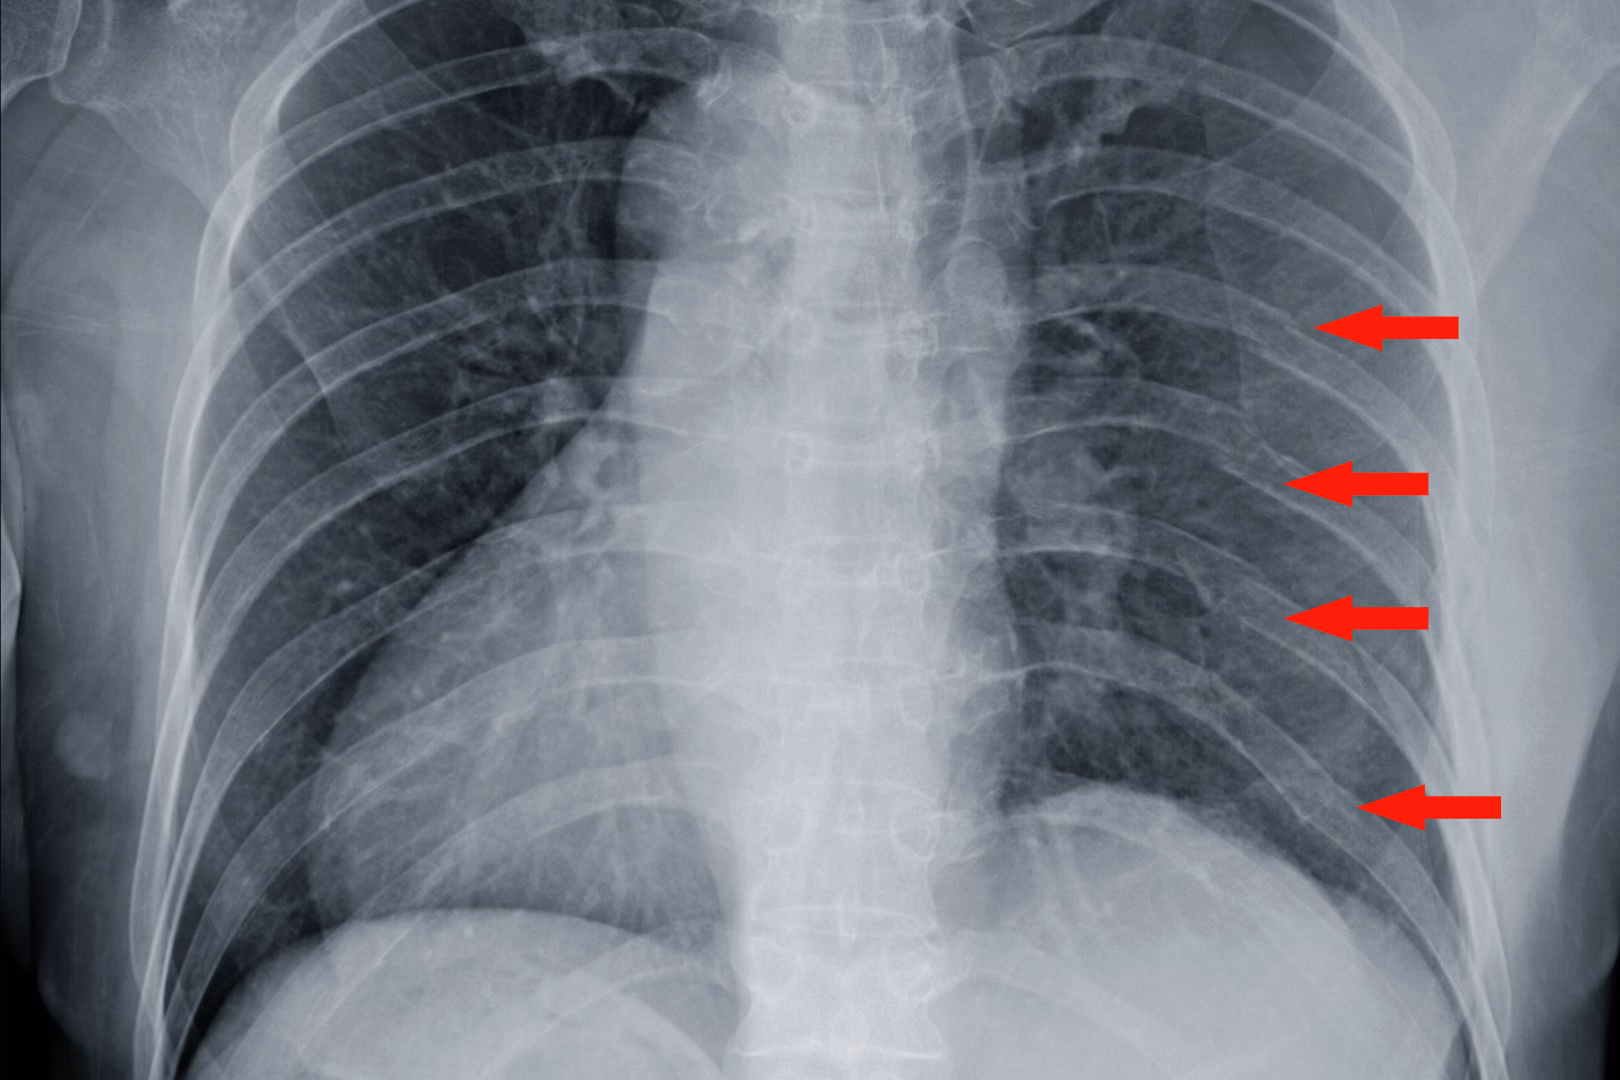

En læge vil typisk kunne stille en formodet diagnose baseret på dine symptomer og en fysisk undersøgelse. For at bekræfte bruddet og udelukke komplikationer kan billeddiagnostik være nødvendig. Et røntgenbillede kan ofte vise bruddet, men det er ikke ualmindeligt, at især revner ikke er synlige. I op til 50% af tilfældene kan et røntgenbillede ikke vise et eksisterende brud. Derfor fravælges det nogle gange, da det sjældent ændrer behandlingsplanen for et ukompliceret brud. Ved mistanke om flere brud, skader på indre organer som lungerne (f.eks. en punkteret lunge/pneumothorax) eller ved alvorlige traumer, kan en CT-scanning give et meget mere detaljeret billede.